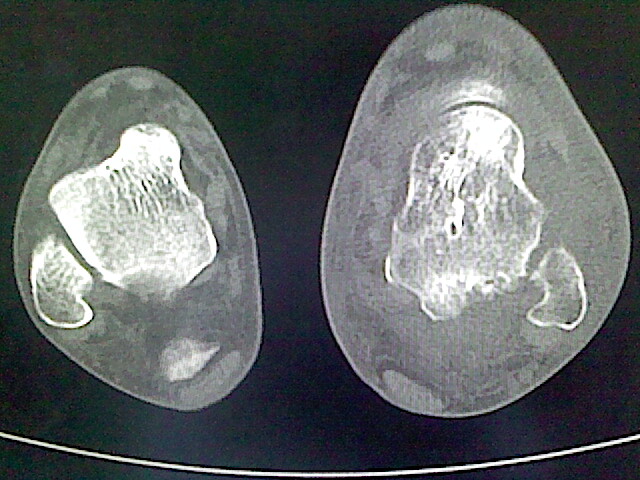

标题: CT16814:男,76岁,左小腿疼痛,不能站立 大家给看看 [打印本页]

男,76岁,左小腿疼痛,不能站立

本例骨质改变主要表现为滑膜或韧带区的骨侵蚀融解(胫腓联合区骨质破坏无硬化边),距骨后部骨质破坏区有硬化边及死骨样改变.所以,本例考虑关节结核可能性大,绒毛膜结节性滑膜炎多发于中年,且极少见于膝髋以外的关节,骨质硬坏也以压陷吸收为主,有明显的硬化边,骨膜增生呈结节状(可以mr鉴别),所以本例暂除外.

另不除外可引起相似表现的其他炎症如布氏杆菌性关节炎等